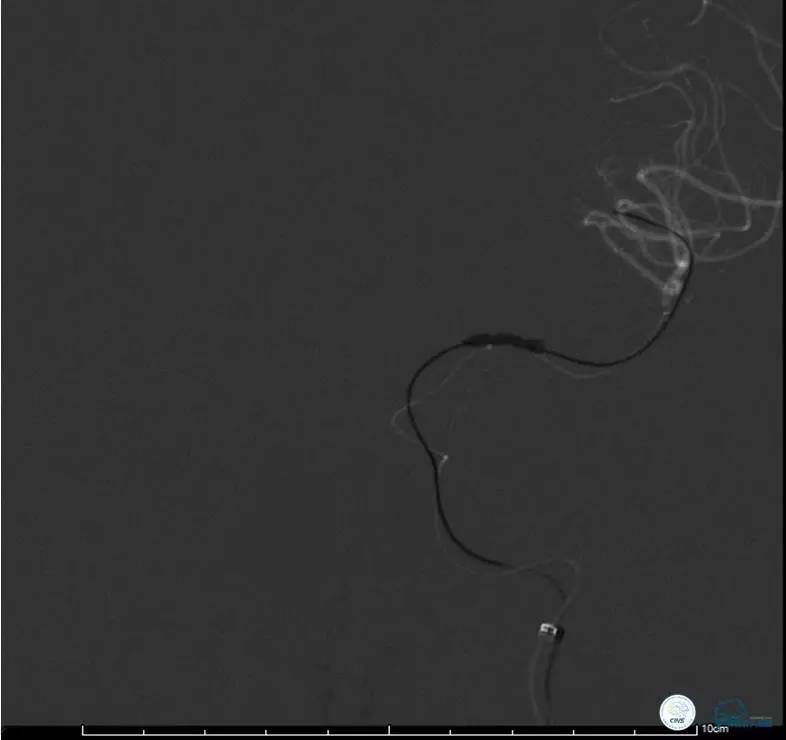

造影评价血管、判断闭塞段,微导丝谨慎穿过闭塞段,微导管造影,交换技术,球囊扩张,Enterprise支架。在后扩张时导丝刺破M3段血管,蛛网膜下腔出血(SAH)。

微导管进入破裂血管,栓塞弹簧圈1枚,出血停止,结束手术。继续双抗,术后2天肌力2级,神经功能恢复明显加快。

半年后复查造影,无支架内再狭窄,可见弹簧圈,患者恢复至自己柱杖行走。